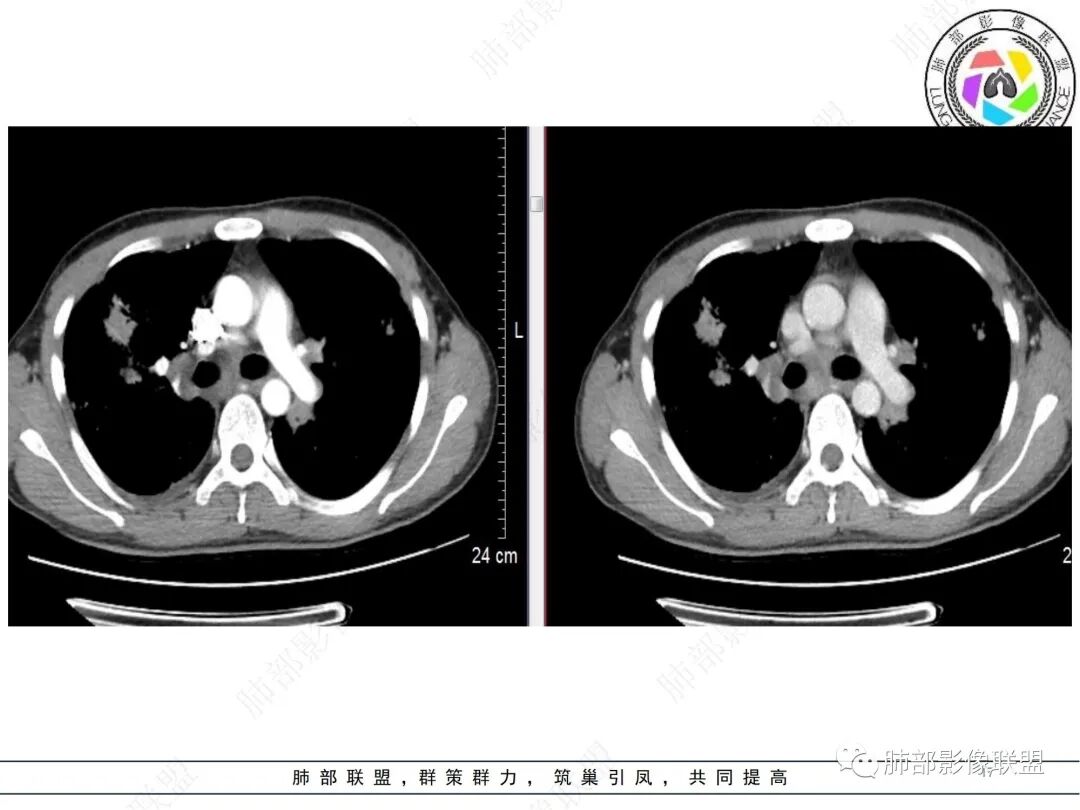

年轻男性,咳嗽咳痰一周;肺部表现:两肺可见团块影,大部分沿胸膜下分布,团块状病灶周围可见散在小结节,双侧肺门及纵隔淋巴结肿大,增强轻中度强化,首先会考虑结节病,其次把隐球菌及结核放前面考虑,结合相关实验室检查;最后淋巴瘤及肺腺癌肿瘤性病变也要考虑。

支气管血管束、胸膜下分布走形,实变似乎多结节融合,双肺门及纵隔淋巴结肿大,增强有血管造影征,影像重,临床症状轻,不太支持结核,考虑结节病,鉴别淋巴瘤。

双肺多发结节及团块影,大部分位于胸膜下,纵隔及肺门多发肿大淋巴结,有融合,增强后结节轻度强化,考虑结节病,鉴别淋巴瘤

青年男性,咳嗽,咳痰一周,双肺多发结节,周围较多小叶中心结界,双肺门淋巴结肿大,纵隔淋巴结肿大,考虑结节病,肿标阴性,鉴别结核,淋巴瘤。

男,咳嗽咳痰一周,肿标阴性,双肺多发胸膜下为主斑片结节状影,小叶中心结节,轻度强化,双侧锁骨上纵隔双肺门多发肿大淋巴结,考虑结节病,鉴别淋巴瘤结核

两肺多发结节及团块,沿支气管血管及胸膜下分布,部分融合,星系征,增强延迟强化,两肺门及纵膈淋巴结肿大,考虑结节病

中年人,咳嗽咳痰一周,双肺多发结节及团片影,大部分位于胸膜下,部分团片状阴影似由小结节融合而成,纵隔及肺门多发肿大淋巴结,有融合,增强后淋巴结轻度强化,未见明显坏死,考虑结节病,鉴别淋巴瘤。

2.影像特点:双肺多发实变,结节状、斑片状、斑点状影,成簇分布趋势,密度不均(部分密度较高),多数位于胸膜下或支气管血管束周围,与支气管关系密切,部分气管壁钙化,部分实变影周围多发弥漫粟粒结节呈星系征样改变,呈轻度渐进性强化,未见空洞。双肺门及纵隔淋巴结肿大,并显示融合,其中后纵隔肿大淋巴结间可见血管影穿行。右侧胸膜增厚伴少量胸腔积液。